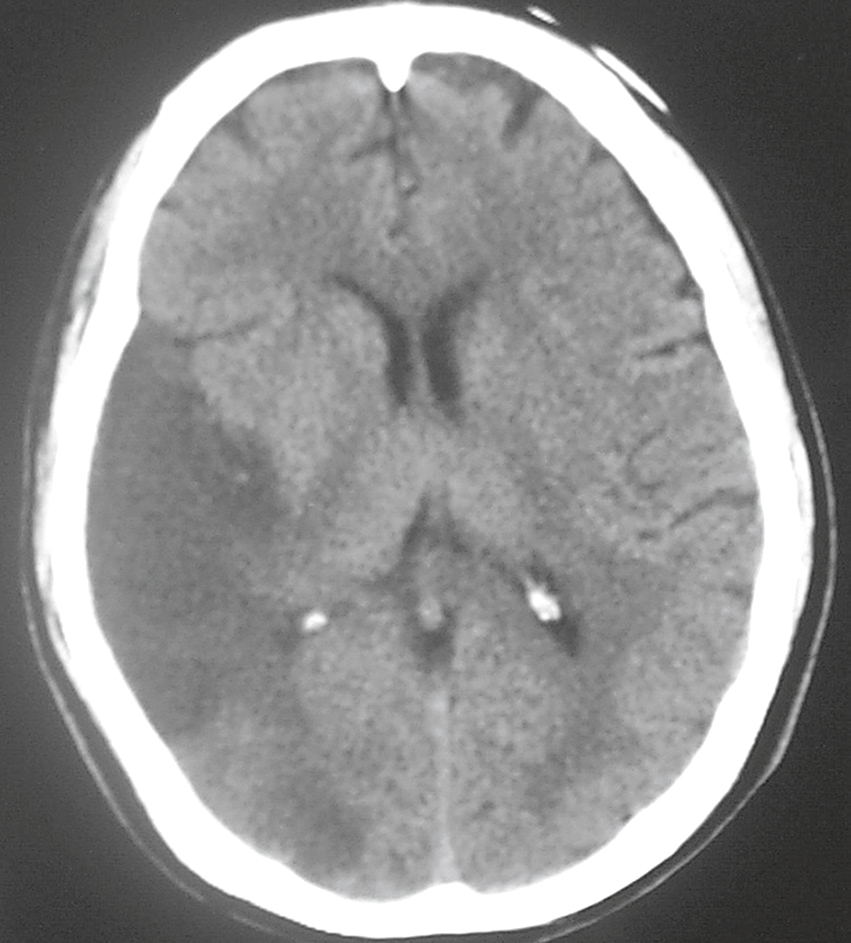

Un patient de 65 ans, droitier est adressé pour un syndrome d’Anton-Babinski depuis 3 jours. Vous suspectez un infarctus cérébral et réalisez le scanner suivant (fig. 32.6). Parmi les territoires artériels suivants, lequel est concerné ?

Scanner cérébral en coupe axiale sans injection de produit de contraste montrant une image spontanément hyperdense localisée dans le noyau lenticulaire gauche, évoquant un hématome intracérébral profond. On note un effet de masse modéré avec effacement partiel des sillons corticaux adjacents, sans engagement ni déplacement majeur de la ligne médiane. L’aspect hémorragique est net, bien limité, sans extension ventriculaire visible. La calcification physiologique des plexus choroïdes est également visible de manière bilatérale au niveau des ventricules latéraux. L’ensemble est compatible avec une hémorragie hypertensive survenue dans le territoire des artères perforantes.